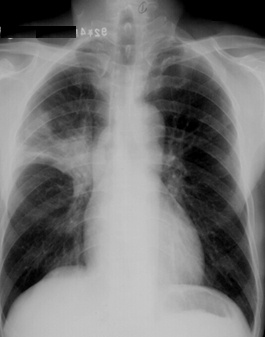

斑片状阴影位于双肺尖,根据公式诊断浸润性肺结核